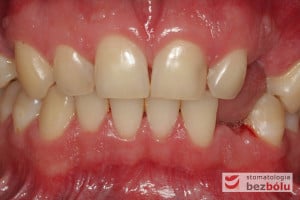

Młody pacjent w wieku lat 28 po wstępnym rozpoznaniu, ze zdiagnozowanym złamaniem kła zarówno górnego jak i dolnego, został skierowany na terapię implantoprotetyczną, prowadzoną przez lekarza dentystę Marcina. W świetle braku możliwości wykonania ekstruzji ortodontycznej i zachowawczego podejścia do leczenia, podjęto decyzję o usunięciu obu zębów, zastosowaniu ułatwiającej gojenie procedury A-PRF i przygotowaniu pacjenta do zabiegu implantologicznego, dodatkowo uzupełnionego o wprowadzenia implantu w miejscu braku zębowego w pEdytujozycji pierwszego przedtrzonowca w szczęce po stronie prawej.

Procedurę chirurgiczną rozpoczęto od sprawdzenia przylegania szablonów do zębów pacjenta oraz znieczulenia miejscowego. W kolejnym kroku, przy pomocy specjalnie przeznaczonego do tego celu zestawu wierteł, wypreparowano krążki dziąsła punktowo odsłaniające kość a następnie poprzez tuleje prowadzące, z najwyższą precyzją, opracowano łoże implantu. Kulminacyjny moment zabiegu, czyli wprowadzenie wszczepów MIS C1 również odbyło się poprzez szablon, gwarantując precyzyjną lokalizację implantów. Zwieńczeniem całej procedury było przyszycie uprzednio wypreparowanych krążków śluzówkowo-okostnowych. Tuż po zabiegu, celem weryfikacji poprawnej pozycji implantów, wykonano zdjęcie ortopantomograficzne. Podczas wizyt kontrolnych, pacjent nie skarżył się na żadne dolegliwości bólowe, nie wystąpił obrzęk, a zreponowane we właściwych miejscach fragmenty dziąsła nie wykazywały oznak martwicy, co świadczyło o ich ponownym ukrwieniu i wgojeniu się. Wszystkie te przesłanki jasno wskazują na skuteczność zastosowania techniki komputerowej nawigacji w implantologii.